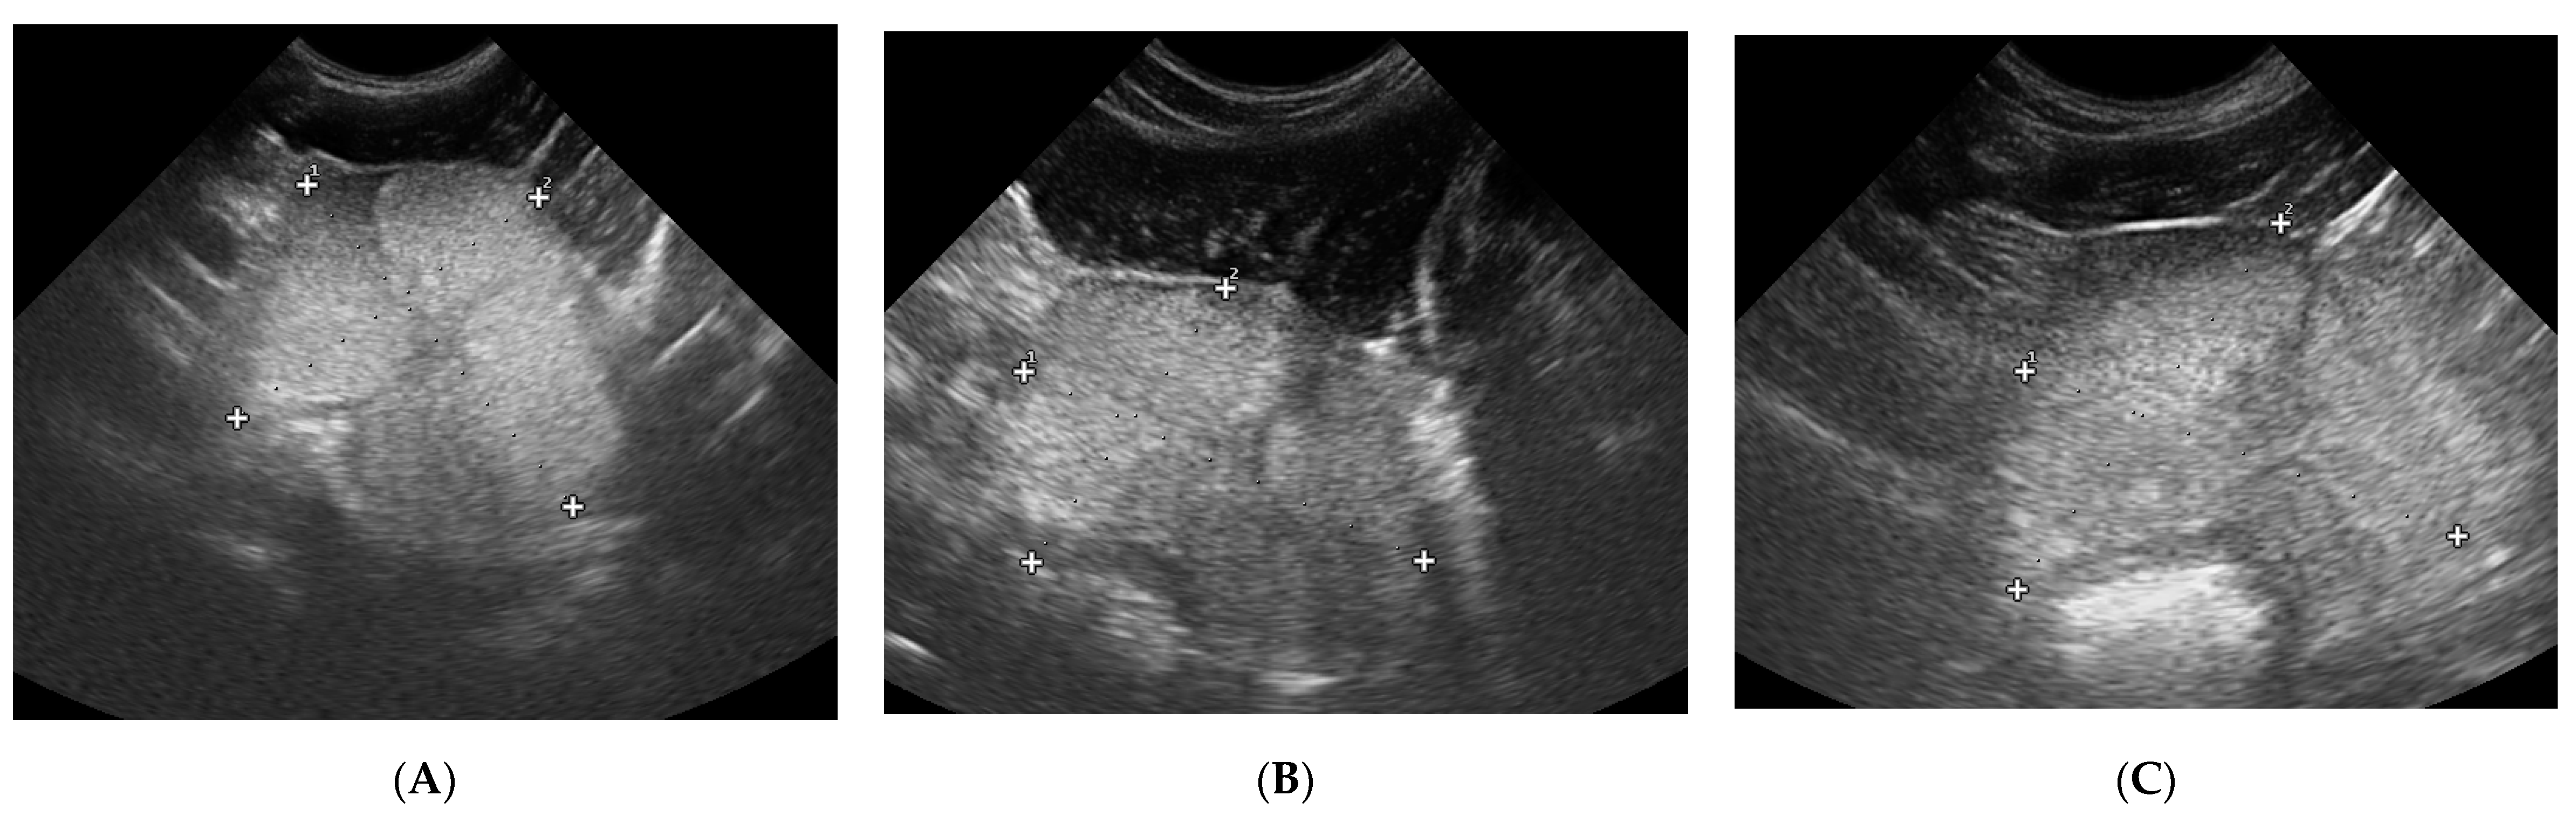

3.1. Prostate B-Mode Appearance

3.2. Doppler Ultrasonography of the Prostatic Artery